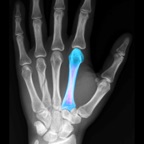

BoneGauge allows you to approximate an individual's bone density and quality from a mobile platform. BoneGauge helps you make measurements of cortical thickness of the second metacarpal from either hand or wrist x-rays. Use your smart phone camera to take a photo of the second metacarpal on an x-ray, or make measurements from an image saved in your photo library.

BoneGauge accurately calculates 2nd metacarpal cortical percentage (2MCP) in a semi-automated fashion. 2MCP has been shown to correlate with hip bone mineral density and T scores from DXA scans. Measurements made in the app will be uploaded to a central database. When combined with a patient's age, gender, and DXA score, past measurements will also help the improve the accuracy of future measurements.

This app allows you to estimate an individual's global T score in an office or hospital setting, by simply taking a photo of the 2nd metacarpal. While this measurement may not completely replace DXA, it may help a clinician screen a patient's bone quality to assist in treatment decisions and determine who may benefit from further bone density testing or osteoporosis treatment.

• Screenshot #1 pour BoneGauge